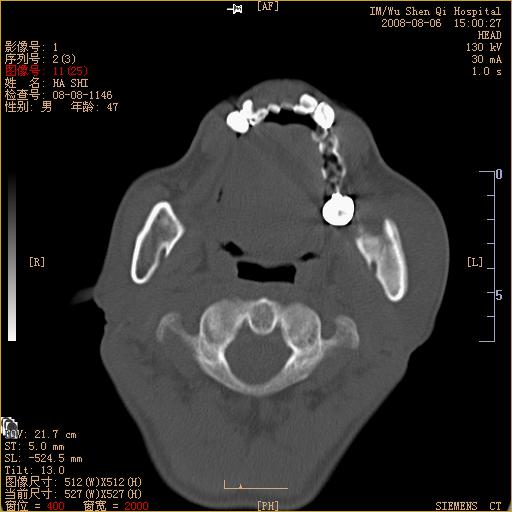

标题: CT15051:男 47岁 左下颌角部肿痛一周 [打印本页]

标题: CT15051:男 47岁 左下颌角部肿痛一周

骨质破坏,无硬化边,周围软组织肿胀,占位

左下颌骨感染性病变,牙源性可能。

左侧下颌智齿阻生。

考虑左下颌骨骨髓炎。